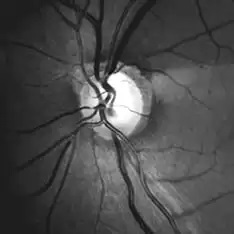

Glaucoma is a condition that causes irreversible vision loss typically due to unusually high pressure in the eye. It is among the top three causes of blindness in India. Unfortunately, people do not notice any change in vision until the condition is in the advanced stages, which is why glaucoma is often referred to as a silent thief of vision.

Regular comprehensive eye checkups are the only way to fight glaucoma vision loss. People at risk include individuals who are over 40 years of age, anyone with a family history of glaucoma, persons having myopia and those with diabetes, hypertension or thyroid.

At Laxmi Eye Hospital, we offer complete eye examination, including glaucoma vetting. Our glaucoma experts’ team is headed by Dr. Rita Dhamankar, who is internationally trained and a pioneer in introducing advancements in glaucoma treatment and surgery in our country.

Don’t compromise on better eye care. Always visit an experienced glaucoma specialist. Visit glaucoma specialist in Navi Mumbai, Dombivli & Kharghar at Laxmi Eye Hospital.